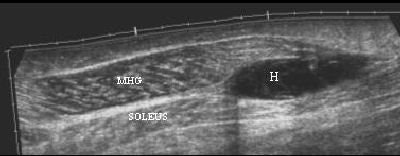

![]() |

A 35-year-old male with a partial rupture of the medial head of the gastrocnemius at the musculotendinous junction. Top, the longitudinal US image shows the medial head of the gastrocnemius muscle with partial discontinuity of the muscle fibers (double arrows). A small hypoechoic fluid collection (single arrow) is noted. G = gastrocnemius muscle, S = soleus muscle. Below, the longitudinal US image one week later shows a hyperechoic fluid collection (arrows). This fluid can be considered as most likely representing flesh blood.